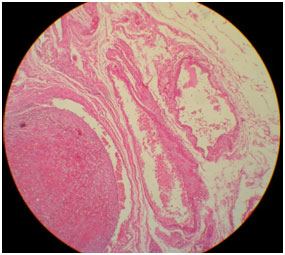

On microscopic examination, there were cavernous vascular spaces, solid spindle cells attached to vessel walls and vacuolated epitheloidendothelial cells [Table/Fig-5,6]. The lesion was well circumscribed, highly cellular with vascular proliferation and slit like spaces [Table/Fig-5,7]. There were few lymphocytes and eosinophils. Larger thin walled vessels with RBCs and areas of hemorrhage were also appreciated. The lesion did not show any cellular atypia and was well circumscribed without infiltration to surrounding structures. Histopathological diagnosis of vascular lesion i.e., spindle cell haemangioma was given. Immunohistochemistry (IHC) was done for the markers CD- 34 and CD- 31 for evaluation of origin of these spindle cells which were triple positive. Pericytes with surrounding blood vessels, split like vascular spaces lined by endothelial cells were positive for CD-34 and cells in vascular channels near endothelial lining were positive for CD 31 [Table/Fig-8] [1].

H&E 4X Histopathology slide showing dilated vascular spaces adjacent to solid spindle cell areas